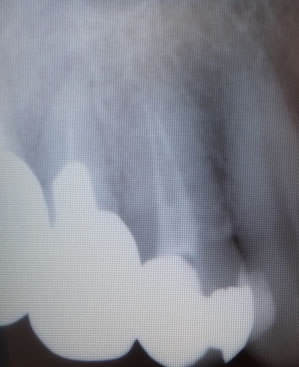

この歯も「痛くてグラグラするので抜いて下さい!」と来院されて、、、

抜いた直後は細い線(クラック)があっただけだったのですが、そのクラックに探針をさすとパカンと開いてきました!!!

(撮影したのは時間がたってからです) |

2つに割れてはいなかったので、レントゲンでは???でした、、、

歯の動揺が尋常ではなかったので抜歯したのですが、やはり正解でした! |

この位に真っ2つに割れていたらレントゲンで確認出来るのですが、、、

クラックのみではレントゲンで確認出来ない事も多いです!!!